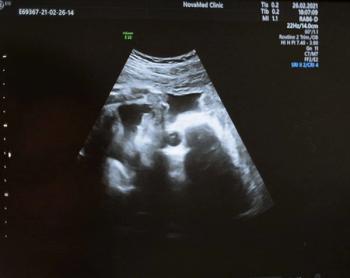

Emerging research shows that a multiple time-series deep learning model assessment of CT images provides 20 percent higher sensitivity than a delta radiomic model and 56 percent higher sensitivity than a clinical model for prognostic evaluation of ground-glass nodules.